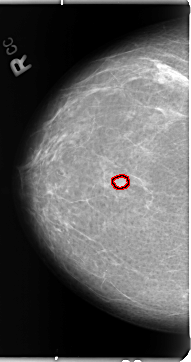

B_3103_1.RIGHT_MLO

RIGHT_MLO LINES 4776 PIXELS_PER_LINE 2680 BITS_PER_PIXEL 12 RESOLUTION 50 OVERLAY

FILE: B_3103_1.RIGHT_MLO.OVERLAY

TOTAL_ABNORMALITIES 1

ABNORMALITY 1

LESION_TYPE MASS SHAPE OVAL MARGINS CIRCUMSCRIBED-ILL_DEFINED

ASSESSMENT 3

SUBTLETY 3

PATHOLOGY BENIGN

TOTAL_OUTLINES 1

BOUNDARY